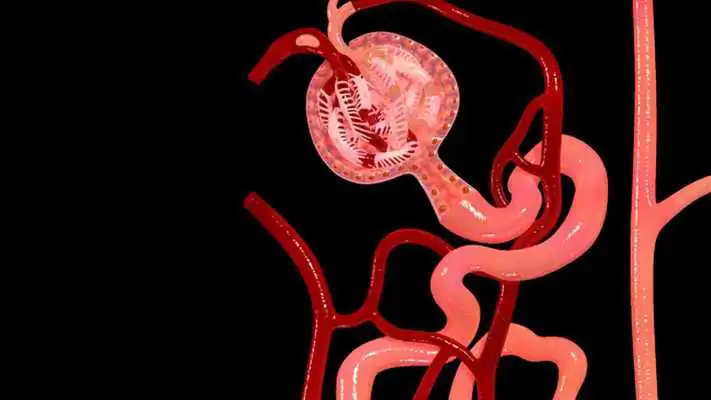

Nephron Blood Vessels 3D

Nephron Blood Vessels 3D

DESCRIPTION

Play this online game named Nephron Blood Vessels 3D.

Nephron Blood Vessels 3D - Key Features :1) You can Zoom and Rotate the 3d model.

2) Take apart to understand the anatomy better.

3) Each layer or object can be made Glassy to see through.

4) Label or Title every object or layer.

5) Analyse feature allows educators for show special focus on a specific part.